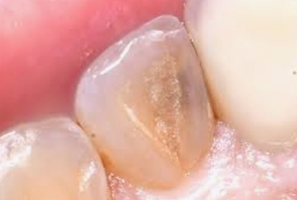

• C1:エナメル質内のう蝕

歯の表面のエナメル質に限局したう蝕です。

ほとんど痛みなど自覚症状を伴わないことから、自ら気付かないことが多いため、歯科医院での定期的な検診により早期発見されることが重要となります。

〈治療法〉

う蝕部分を除去し、コンポジットレジンと言われる歯の色調に合った合成樹脂の充填を行います。